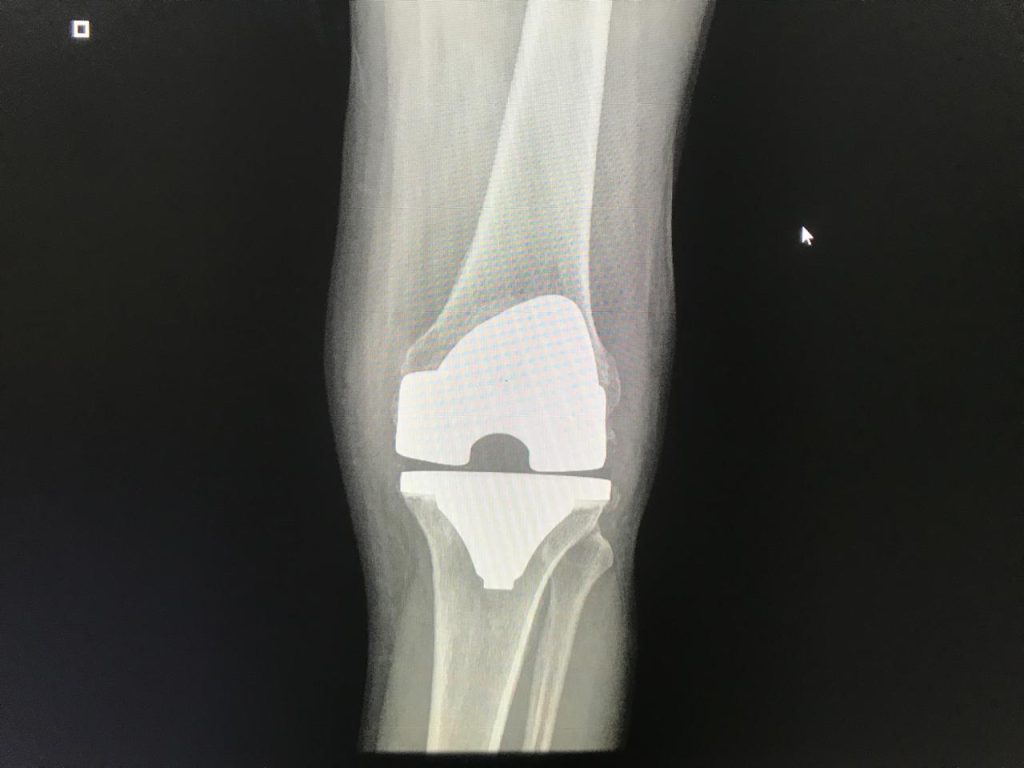

Gracias a un procedimiento de reemplazo total de rodilla realizado con precisión y tecnología avanzada, nuestro paciente pasó de un dolor incapacitante a iniciar su rehabilitación con excelentes resultados desde el primer día postoperatorio.

Después de su cirugía de rodilla, nuestro paciente recuperó la movilidad, la confianza y la libertad de disfrutar cada paso. Con la experiencia del Dr. Yesith Fernando Cristancho, especialista en cadera y rodilla, tú también puedes dejar atrás el dolor y volver a vivir plenamente. Agenda tu valoración y da el primer paso hacia tu recuperación.